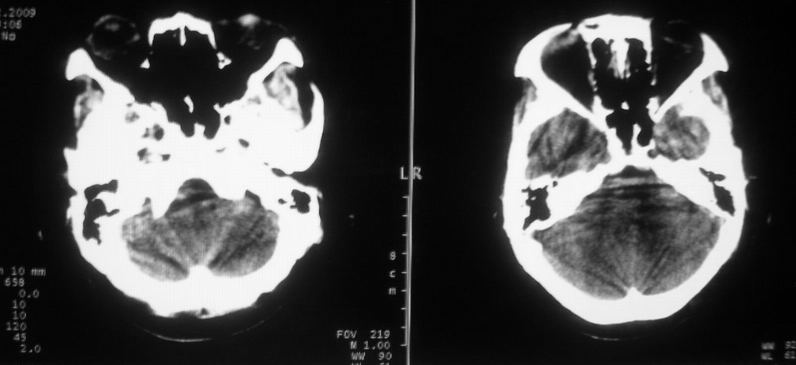

标题: CT18148:女,44岁,头痛数月。 [打印本页]

女,44岁,头痛数月。

考虑一氧化碳中毒缺氧,形成的

考虑脑肿瘤,建议ct增强或mri。

右侧额叶占位性病变,考虑脑肿瘤;建议行进一步检查。

右侧额叶占位性病变,考虑脑膜瘤可能性大;建议行进一步检查。

囊性脑膜瘤